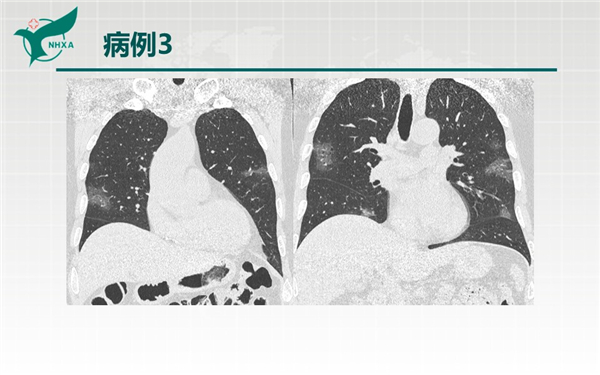

幻燈片10.jpg